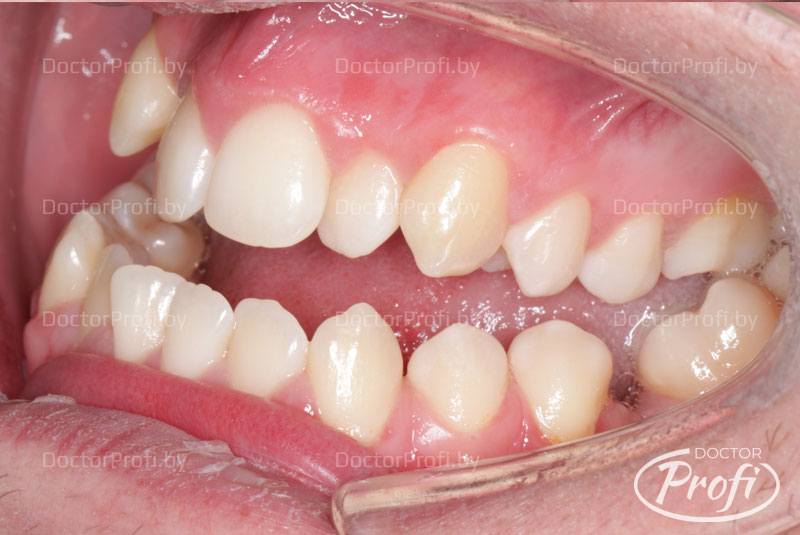

После